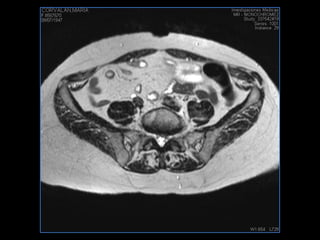

LIC ALEJANDRA GALVEZ RM DE ABDOMEN

PROTOCOLO pelvis SAG T2, Y FAT SAT (FINOS) AXIAL T1  AX FAT SAT CON   GADOLINIO :  AX T1 Y COR T1 SAT: NO  FASE: RL THK: 3MM  COIL:  GAP: (FACTOR 1.4) 1MM FOV: 40 CM NEX:2 SINCRONIZACION RESPIRATORIA EN 3 O 4 CICLOS ALE

resonancia de abdomen